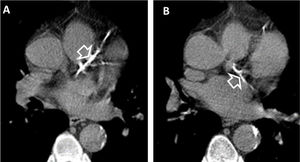

(A and B). Coronary artery calcifications at baseline LDCT. Severe coronary artery calcifications in the anterior interventricular artery (white empty arrowhead A) and left circumflex artery (white empty arrowhead B) at baseline LDCT in a 69-year-old man from NLST who died of atherosclerotic heart disease (ICD code I251) 226 days after randomization.